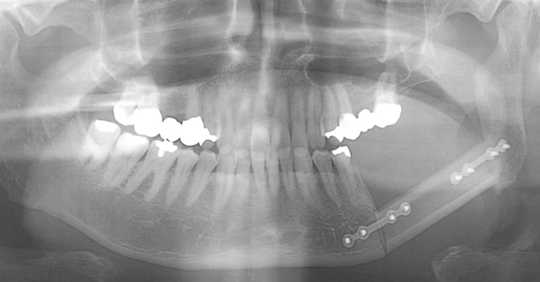

肩甲骨皮弁による下顎骨再建例(本学顎口腔外科学講座原田教授による)

矢印内の広範に下顎骨を切除した後に、肩甲骨皮弁で再建し、移植骨にきざみを入れることで、本来の下顎骨の形態に近づけている。

顔貌の形態が良好に保たれている。

デンタルインプラントを埋入し、咬合機能の改善がはかられている。

腓骨皮弁による顎骨再建例(本学顎口腔外科学講座原田教授による)

病変部分を切除。

プレート除去後、デンタルインプラントを埋入し、咬合機能の改善がはかられている。